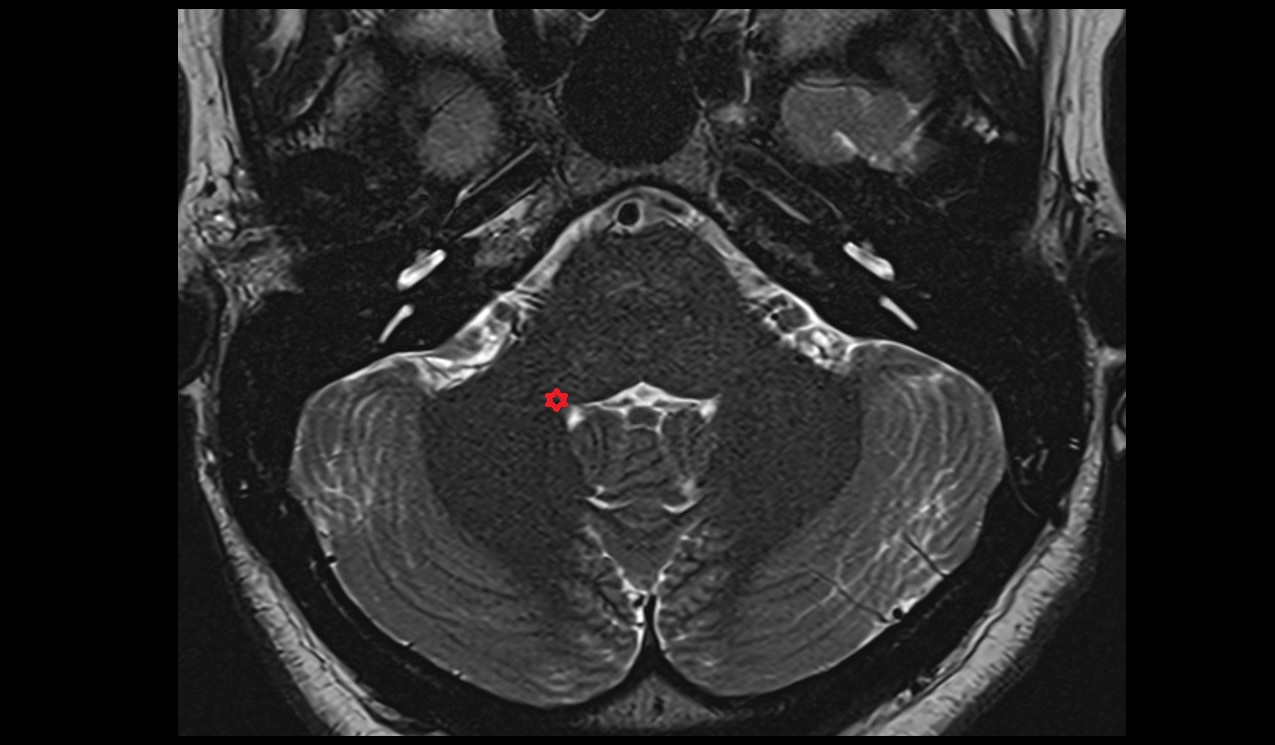

- Cerebellum

- Middle cerebellar peduncle

- Pontocerebellar cistern